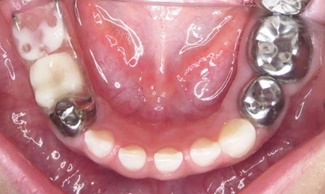

A la exploración intrabucal presentó dentición primaria incompleta, múltiples lesiones cariosas activas en molares superiores e inferiores, ausencia clínica de primer y segundo molar primario inferior derecho (Figuras 2, 3 y 4). Previo consentimiento informado, leído, explicado y firmado por tutora, se rehabilitó cavidad bucal de menor en cuatro citas diferentes mediante técnicas decir-mostrar- hacer y refuerzo positivo.

Figura 2 Fotografía oclusal superior. Se observan lesiones cariosas activas en molares, con destrucción parcial de la corona.

Figura 3 Fotografía oclusal inferior. Se observan lesiones cariosas activas en molares inferiores lado izquierdo y ausencia clínica de molares lado derecho.